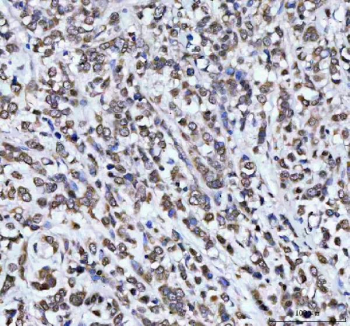

Immunohistochemical staining of AHCY using anti-AHCY antibody. AHCY was detected in a paraffin-embedded section of human breast cancer tissue. Heat mediated antigen retrieval was performed in EDTA buffer (pH 8.0, epitope retrieval solution). The tissue section was blocked with 10% goat serum. The tissue section was then incubated with 2 ug/ml rabbit anti-AHCY antibody overnight at 4oC. Peroxidase Conjugated Goat Anti-rabbit IgG was used as secondary antibody and incubated for 30 minutes at 37oC. The tissue section was developed using an HRP secondary and DAB substrate.